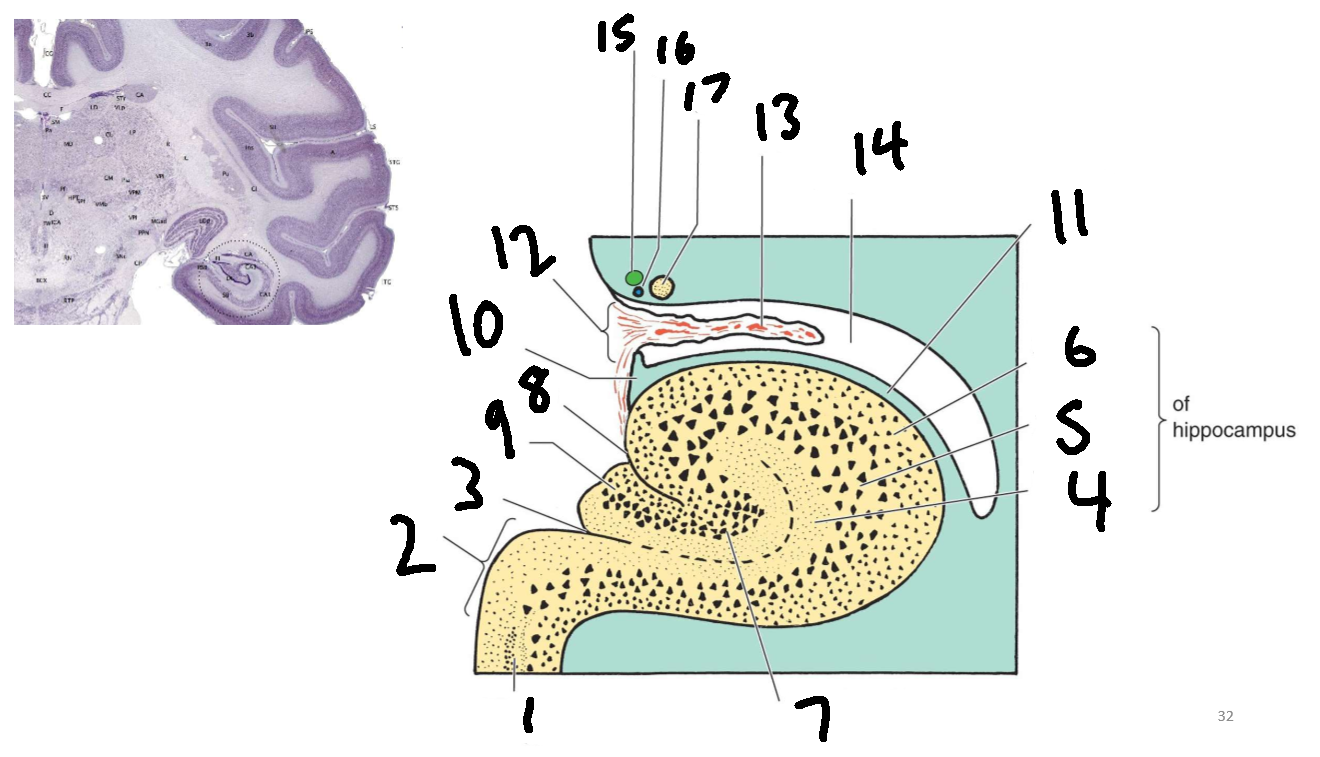

What structure is this?

hippocampus

What is 1?

hippocampus

What is 2?

rhinal sulcus

What is 3?

lateral ventricle

What is 4?

thalamus

What is 5?

entorhinal cortex

What is 6?

perirhinal cortex

What is 7?

parahippocampal cortex

What is 1?

gyrus dentatus

What is 2?

cornu ammonis

What is 3?

fimbria

What is 3’?

alveus

What is the arrow pointing to?

happicampal sulcus

What is ca1, ca2, ca3 and ca4?

fields of cornu ammonis

What is 4?

tela choroidea

What is 5?

stria terminalis

What is 6?

tail of caudate nucleus

What is 7?

temporal horn of lateral ventricle

What is 8?

collateral eminence

What is 9?

collateral sulcus

What is 10?

parahippocampal

What is 11?

entorhinal area

What is 12?

subiculum

What is 13?

lateral geniculate body

What is 1?

parahippocampal gyrus

What is 2?

subiculum

What is 3?

hippocampal sulcus

What is 4?

molecular layer

What is 5?

pyramidal layer

What is 6?

polymorphic cell layer

What is 7?

granule cell layer of dentate gyrus

What is 8?

fimbriodentate sulcus

What is 9?

dentate gyrus

What is 10?

fimbria of hippocampus

What is 11?

alveus

What is 12?

choroid fissure

What is 13?

choroid plexus

What is 14?

temporal horn of lateral ventricle

What is 15?

stria terminalis

What is 16?

thalamostriate vein

What is 17?

tail of caudate nucleus